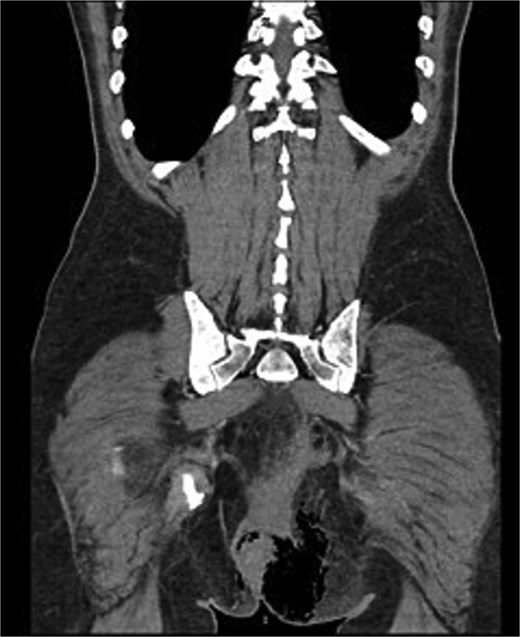

We present the case of a 47-year-old male with no prior medical history who arrived at the Emergency Department with a rapidly evolving perianal abscess (Fig. 1). Within hours, he developed Fournier’s gangrene secondary to an undiagnosed rectal neoplasm (Fig. 2).

Histopathological analysis revealed a moderately differentiated adenocarcinoma. Colonoscopy showed no additional lesions and tumour markers were normal. PET-CT excluded distant disease. Pelvic MRI demonstrated involvement of the left levator ani, mesorectal fascia, and suspicious lymph nodes, suggestive of cT4bN1a disease (Fig. 4).